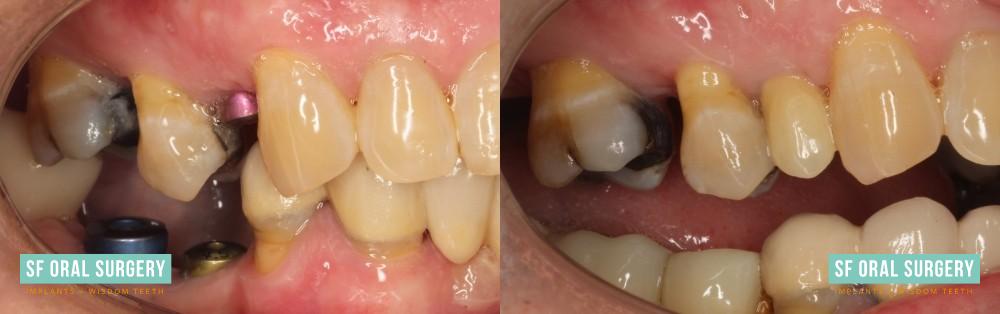

Patient 2

The patient presented with numerous decayed and broken teeth and expressed a strong desire for improved oral health. Ultimately, we placed five implants, resulting in a complete restoration of her dentition with a beautiful set of teeth. This case was conducted under the care of Dr. Rittenbach and in collaboration with Dr. Courtney Fitzpatrick.